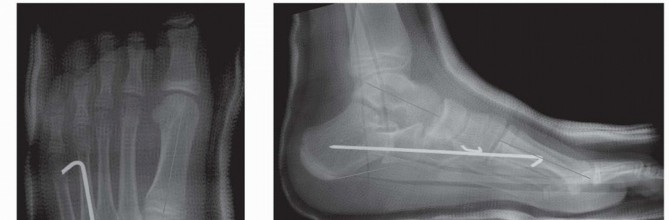

POSTOPERATIVE CARE The incisions are closed with absorbable sutures.A well-padded, short-leg, non-weight-bearing cast is applied and bivalved to allow for swelling overnight. Radiographs in the cast are obtained ( FIG 5).The patient is discharged from the hospital the following day after the bivalved cast is overwrapped with cast material.The patient is immobilized in a below-knee cast and is not permitted to bear weight on the operated extremity for 8 weeks.At 6 weeks, the cast is removed to obtain simulated standing AP and lateral radiographs and to remove the Steinmann pin. Another below-the-knee, non-weight-bearing cast is applied.Upon removal of this cast 2 weeks later, final simulated standing AP and lateral radiographs are obtained. Over-the-counter arch supports are used indefinitely.Physical therapy is rarely needed. ## OUTCOMES The calcaneal lengthening osteotomy has the best reported long-term results of any procedure that has been used to correct flatfoot deformity.It has been shown to correct all components of even severe valgus-eversion deformity of the hindfoot, restore function of the subtalar complex, relieve symptoms, and, at least

theoretically, protect the ankle and midtarsal joints from early degenerative arthrosis by avoiding arthrodesis. ### FIG 5 • Final radiographs in the bivalved cast. A. On the AP view, note the correction of the external rotation deformity at the talonavicular joint as also assessed by the talo-first metatarsal angle. B. The lateral view demonstrates dorsiflexion of the talus, alignment at the talonavicular joint, correction of the talo-first metatarsal angle, and normalization of the calcaneal pitch. (From Mosca VS. Calcaneal lengthening osteotomy for valgus deformity of the hindfoot. In: Tolo V, Skaggs D, eds. Master Techniques in Orthopaedic Surgery: Pediatric Orthopaedics. Philadelphia: Lippincott Williams & Wilkins, 2008:263-276.)